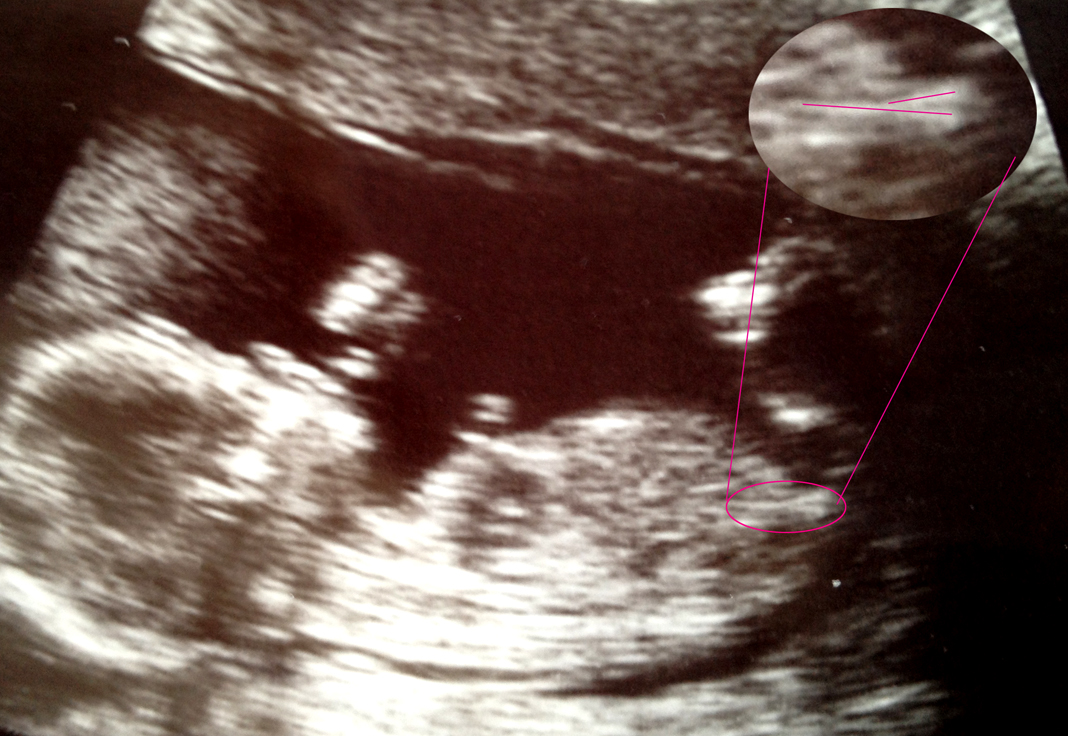

What do you think? Anything there?

Is this a nub

Here's a scan photo I didn't include before: